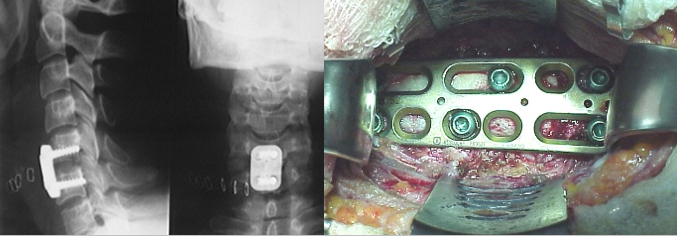

Sistema Cespace La imagen de la izquierda corresponde a la caja montada en el introductor. La imagen contigua muestra el aspecto frontal del implante. Notese aqui y en la imagen anterior el sistema de u;as en corona dispuesto tanto en la porcion superior como inferior de la caja. Estas u;as se incrustan en el hueso vertebral y ofrecen un solido sistema de estabilizacion primaria. La imagen de la derecha corresponde a la vision intraoperatoria de un implante colocado.

Resultados del sistema Cespace. La imagen de la izquierda del montaje superior que aparece a continuacion corresponde a una caja Cespace insertada dos semanas antes. La imagen de la derecha, en la que pueden observarse evidentes puentes oseos corresponde a una caja que fue colocada nueve meses antes de la radiografia. Los resultados en cuanto a estabilizacion primaria y secundaria son excelentes.